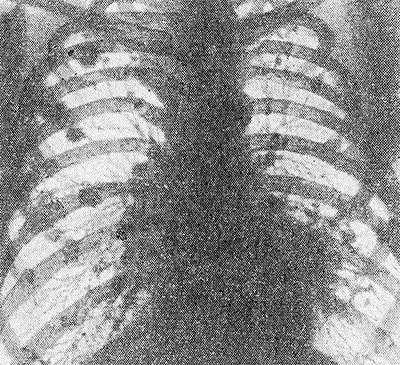

Рентгенограмма грудной клетки больного с синдромом Каплана: видны множественные затемнения округлой формы.

К. с. характеризуется развитием типичного ревматоидного артрита (см.) в сочетании со своеобразными рентгенол, изменениями со стороны легких. Рентгенологически на фоне диффузных, преимущественно интерстициальных, изменений определяются четко отграниченные округлые затемнения от 0,5 до 5,0 см в диаметре, располагающиеся гл. обр. по периферии обоих легких (рис.). С прогрессированием заболевания затемнения постепенно увеличиваются в количестве и размерах. Могут также наблюдаться и другие, присущие ревматоидному артриту, висцеральные поражения (почек, печени, сердца). Особенностью К. с. является обнаружение в сыворотке крови больных ревматоидных факторов (см.).

Характерная рентгенологическая картина синдрома: на фоне диффузных и преимущественно интерстициальных изменений в легких определяются четко отграниченные округлые очаги затемнения размером от 0,5 до 5 сантиметров в диаметре. Они располагаются преимущественно по периферии обоих легких и при прогрессировании процесса имеют склонность увеличиваться в размерах.